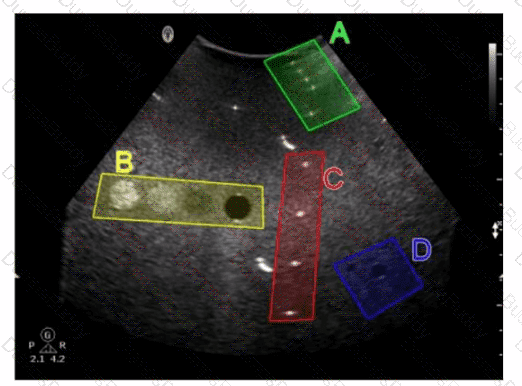

Which target group in this image of a tissue-mimicking phantom is used for gray-scale evaluation?

SPI Question 53

Options:

A.

Option A

B.

Option B

C.

Option C

D.

Option D